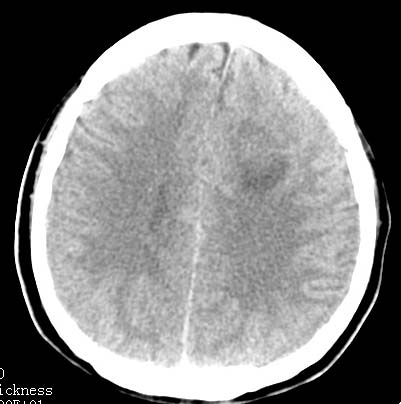

以下是引用clj20在2007-8-29 9:47:00的发言:[br]蛛网膜下腔出血,左侧额叶不均匀密度影,占位效应明显,界限不清。支持:占位性病变,建议增强!

以下是引用xulianj在2007-8-29 20:15:00的发言:[br]蛛网膜下腔出血,左侧额叶不均匀密度影,占位效应明显,界限不清。支持:占位性病变,建议增强!

以下是引用jiangjing在2007-8-29 14:33:00的发言:[br]左侧额叶不均匀密度影[低密度为主,边缘见等密度环环绕]占位效应明显,界限不清。支持:占位性病变,建议增强! [br][br]